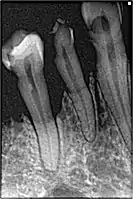

الأشعة السينية عند طبيب الأسنان

يستخدم طبيب الأسنان الأشعة السينية لتصوير الأسنان بواسطة الفيلم ومعرفة الفاسد منها من أجل وضع خطة لترميم الأسنان. إلا أن تحميض الفيلم يأخذ جزء من الوقت. بالإضافة إلى صعوبة تخزين تلك الأفلام وتسجيلها. لذلك طورت طريقة التصوير بالأفلام وبدأت تحل محلها التصوير الرقمي بواسطة المجسات الرقمية. وتحتاج تلك الطريقة تعرض المريض لإشعاع أقل خلال عملية التصوير. وتظهر الصورة مباشرة على شاشة المرقاب.

ويُراعى أثناء أخذ الصور بالأشعة السينية حماية أجزاء جسم المريض الأخرى التي لا تدخل في حيز الفحص من الأشعة بواسطة حوائل رصاصية. كما أن الممرضة التي تعمل على جهاز الأشعة تغادر الغرفة بعد إعدادها المريض للتصوير، وتقوم بتشغيل الجهاز من خارج الغرفة وذلك لكي لا تعرض نفسها للإشعاع. وفي العادة تجري كل ممرضة تدريبا عمليا كل خمس سنوات لمدة يوم واحد لتجديد معرفتها بأصول العمل بالأشعة والأخذ بالجديد في هذا المضمار.